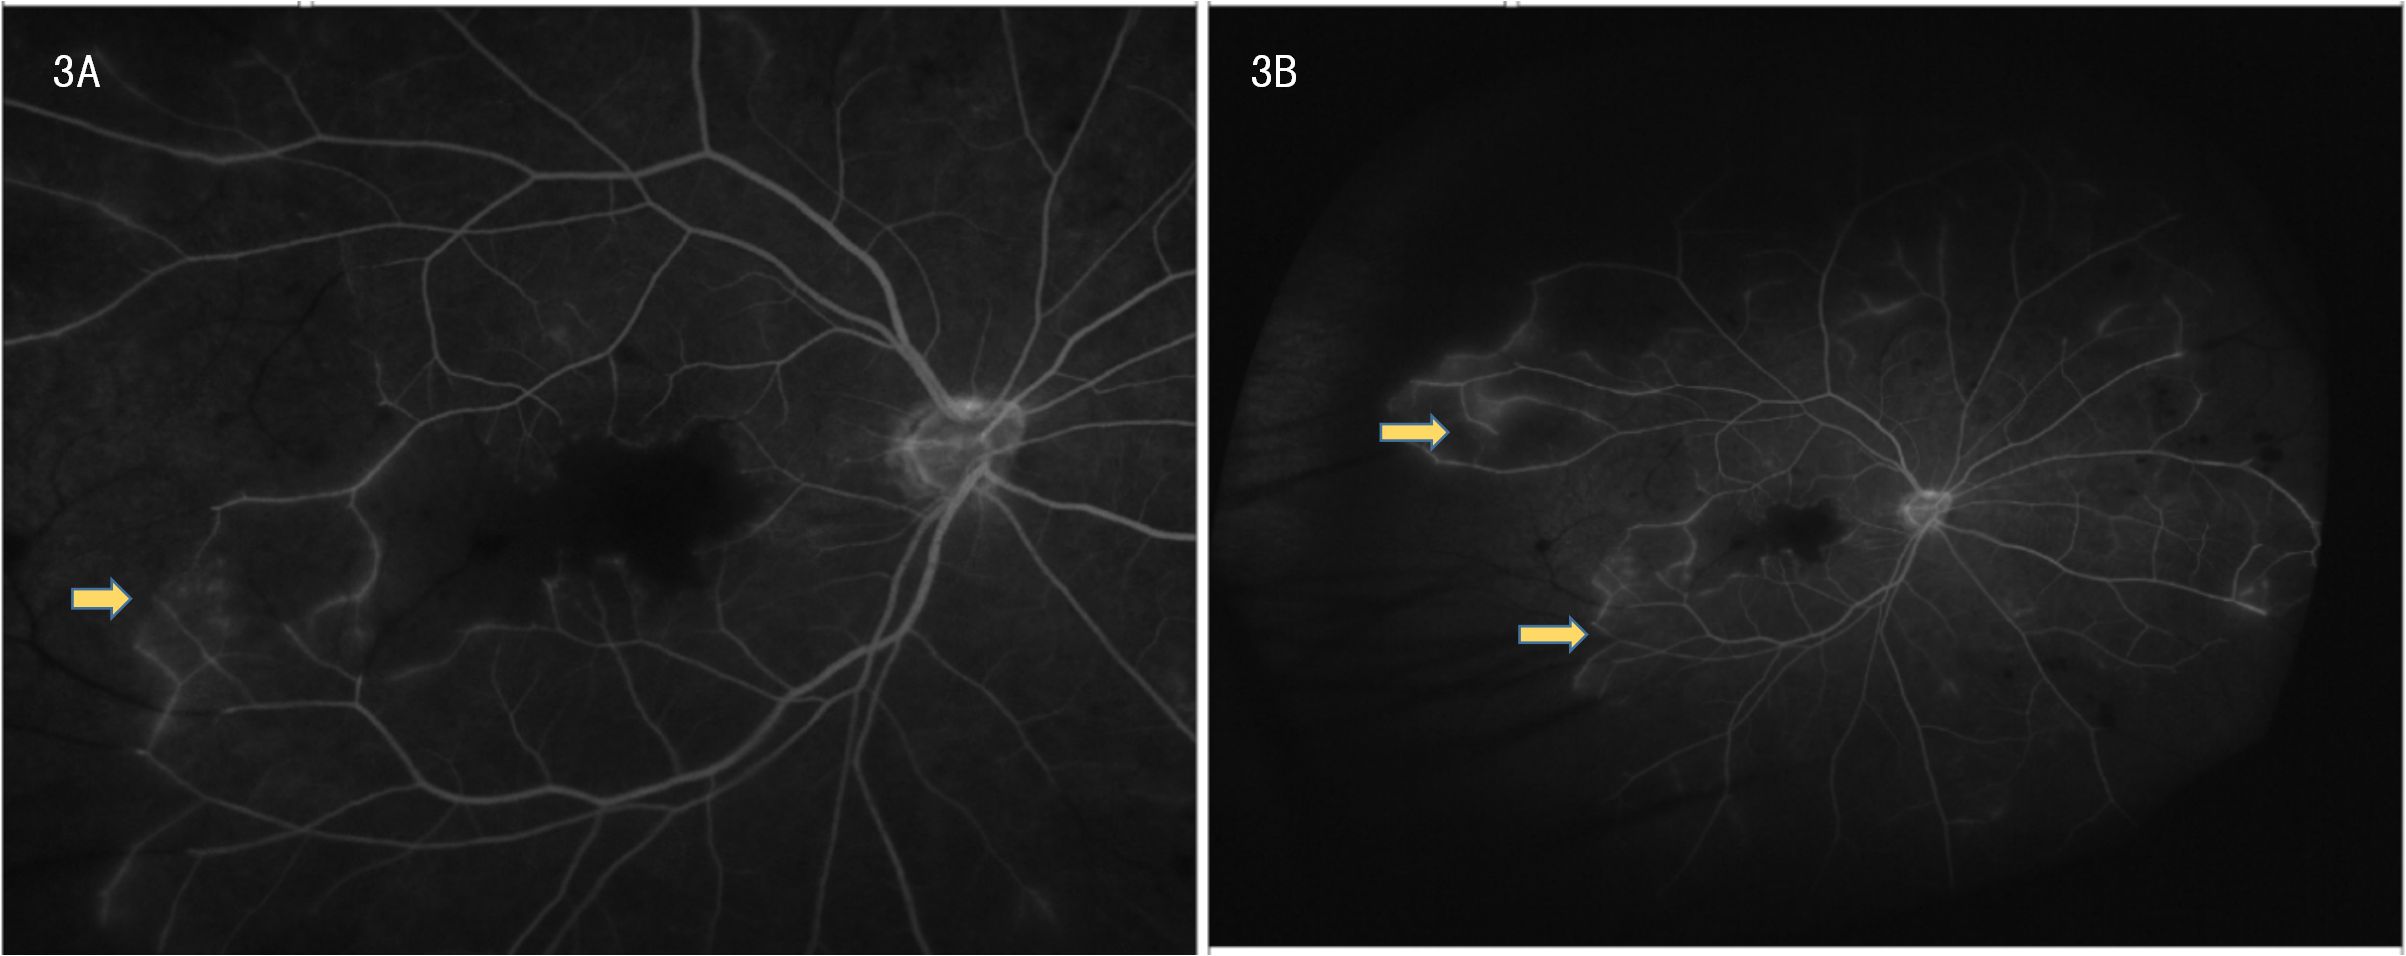

Ophthalmic evaluation revealed significant bilateral vision impairment, with light perception in the right eye and hand movement in the left eye. Intraocular pressure measured 14.5 mmHg in the right eye and 14.2 mmHg in the left eye. Slit-lamp examination demonstrated bilateral clear corneas, normal anterior chambers, round pupils, and clear lenses. Ophthalmoscopy showed bilateral optic discs with normal color and margins, geographic gray-white retinal edema in the macular region, scattered ink-like hemorrhages throughout the posterior pole and peripheral retina, and segmental changes in the peripheral veins. Optical coherence tomography (OCT) confirmed bilateral macular edema, revealing hyper-reflective signals within the inner retinal layers in corresponding areas and hyper-reflective changes in the outer retina at the fovea. FFA indicated normal retinal circulation time but demonstrated extensive peripheral retinal vascular occlusion extending to the macula, along with prominent venous wall staining; these angiographic findings are consistent with occlusive vasculitis exhibiting venous predominance (Figures 3A, B).

Two black and white retinal angiography images labeled 3A and 3B show detailed networks of blood vessels. Yellow arrows indicate specific areas of interest within each photo. Image 3A has one arrow pointing to a vessel, while image 3B has arrows pointing to two different areas.

Figure 3. (A, B) Frosted branch angiitis with fern-like pattern on fundus fluorescein angiography.

Behçet’s disease, a chronic relapsing variable-vessel vasculitis impacting arteries and veins of all sizes, often presents with recurrent oral/genital ulcers, skin lesions, and ocular inflammation, affecting multiple systems. Its pathogenesis likely involves genetic, environmental, and immunologic factors, with HLA-B51 being a key marker linked to severe forms, particularly in East Asian and Mediterranean populations (3). Ocular involvement, especially retinal vasculitis like frosted branch angiitis (FBA), a rare clinical sign characterized by extensive perivascular sheathing and dendritic white sheaths of retinal veins, observable via funduscopy or FFA. FBA is not exclusive to BD and can occur in various infectious or autoimmune etiologies, indicates severe vascular inflammation and carries a poor prognosis if untreated (2). HLA-B51-positive BD patients are at higher risk for such severe ocular manifestations (3).